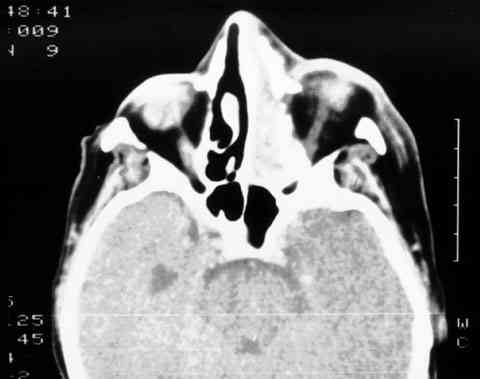

Figura 4

T.A.C. QUE REVELA LA OCUPACIÓN DE LA FOSA NASAL, EL SENO ETMOIDAL Y PARTE DE LA ÓRBITA IZQUIERDA.